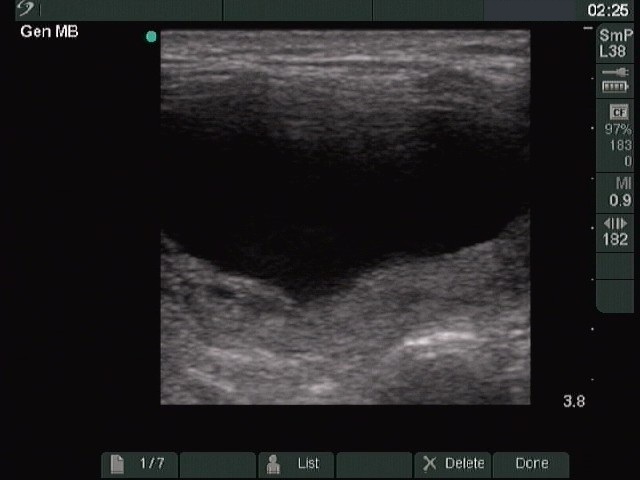

Ultrasonography : the thyroids were echonormal. There was a cystic nodule with an echonormal solid part in the right lobe.

Five sessions of sclerotherapy were performed. We gave 19.8 mL alcohol during five sessions of ethanol sclerotherapy. We demonstrate the first and the third sessions.